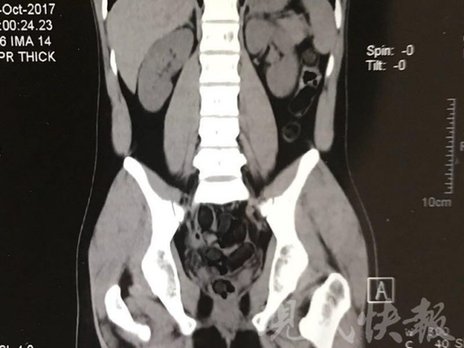

由于毒品在體內(nèi)一旦泄露有可能致命,警方第一時間將阿永帶到醫(yī)院進(jìn)行檢查。CT 掃描的結(jié)果顯示,阿永體內(nèi)布滿了密密麻麻的白色圓柱狀固體,就像一粒粒的蠶蛹。在南京市公安局鼓樓分局二板橋派出所,阿永分四次排出了毒品,毛重369.99克。經(jīng)訊問,阿永交代了自己全部的犯罪事實。目前,阿永已被刑事拘留。